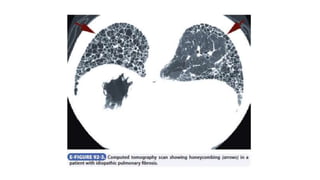

• Ultimately, progressive fibrosis results in honeycombing, an end-stage

finding that is often associated with increased pulmonary vascular

resistance and secondary pulmonary hypertension.

• The diagnostic features on HRCT are peripheral, predominantly basilar

patchy intralobular reticulation, often with subpleural honeycomb

cysts, traction bronchiectasis, and traction bronchiectasis as the

disease becomes more advanced.

histopathologic pattern of usual interstitial pneumonia consists of

patchy interstitial changes alternating with zones of honeycombing,

fibrosis, minimal inflammatory cells, collagen deposition, and normal

lung.